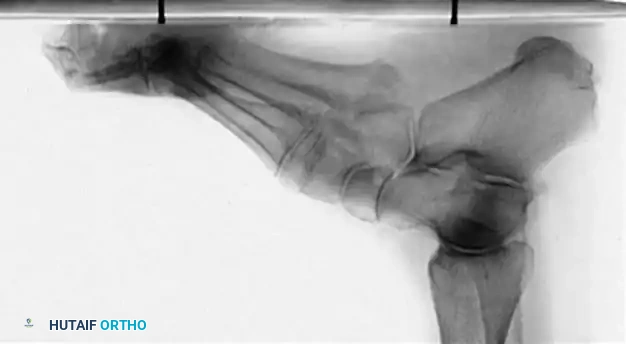

Radiographic Evaluation

Brockway’s 1940 axiom remains true: "Cavus feet should never be operated upon until radiographs with the patient standing have been taken."

Standard weight-bearing anteroposterior (AP) and lateral radiographs of the foot, along with a weight-bearing AP of the ankle, are required.

Key Radiographic Parameters:

* Meary’s Angle (Talus-First Metatarsal Angle): Normally 0 degrees. In a cavus foot, the angle is convex upward (apex dorsal), indicating midfoot/forefoot equinus.

* Calcaneal Pitch: Normally 15 to 20 degrees. In a cavus foot, it is significantly increased (>30 degrees).

* Hibbs Angle: The angle between the longitudinal axis of the calcaneus and the first metatarsal. It approaches 90 degrees in severe cavus (normal is ~140 degrees).

* Talonavicular Coverage: Assessed on the AP view to quantify midfoot adduction.

Fig. 7: Standing lateral radiograph demonstrating an increased calcaneal pitch and a severe apex-dorsal Meary's angle.